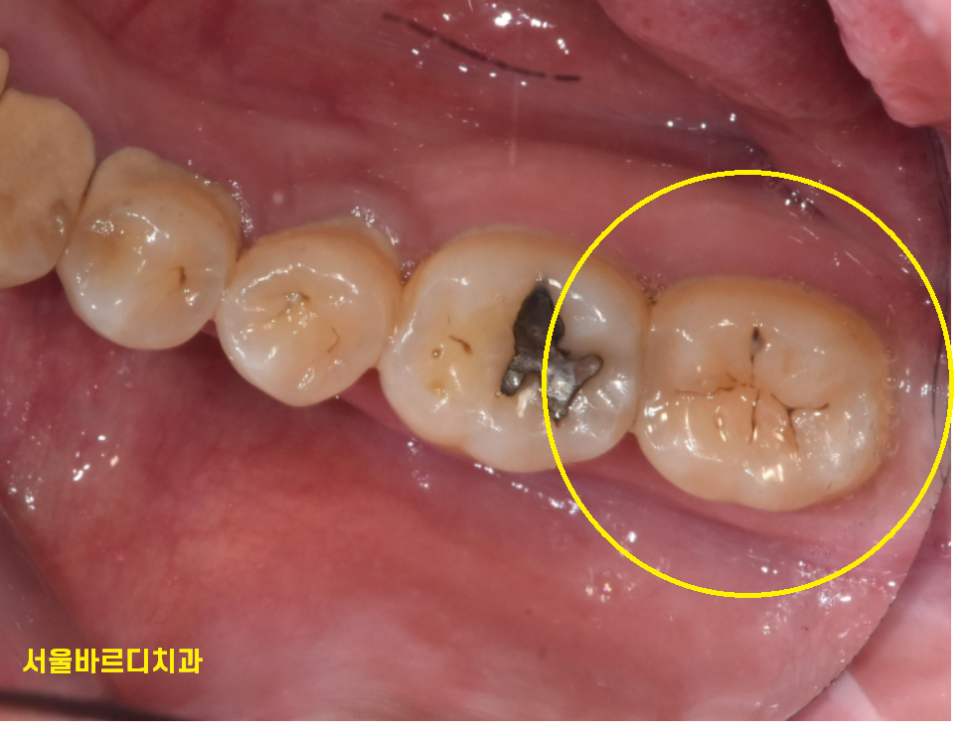

그럼 이건 충치일까요?

방금 보았던 충치보다 검정색이

좀더 진하게 보이죠~?

충치는 맞습니다!

그렇지만 역시나

치료를 안해도 된다!!!

단! 관리만 잘해준다면!! (핵심)

관리해준다면 충치가 정지합니다.

정지성 우식이라 표현하는데요

검은 점이 보인다고

모두 충치 치료를 할 필요는 없답니다.

길동 치과에서는 이런 검은 점 충치는

치료하지 않습니다.

정기검진을 통하여 지켜보고

충치가 커지거나 하였을 때 치료를 시작하죠~!